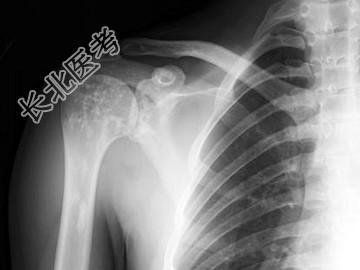

- 单项选择题男,34岁, 体检摄片如图所示,最可能的诊断是 ( )

A、氟骨症

B、转移性骨肿瘤

C、骨样骨瘤

D、骨岛

E、骨斑点症